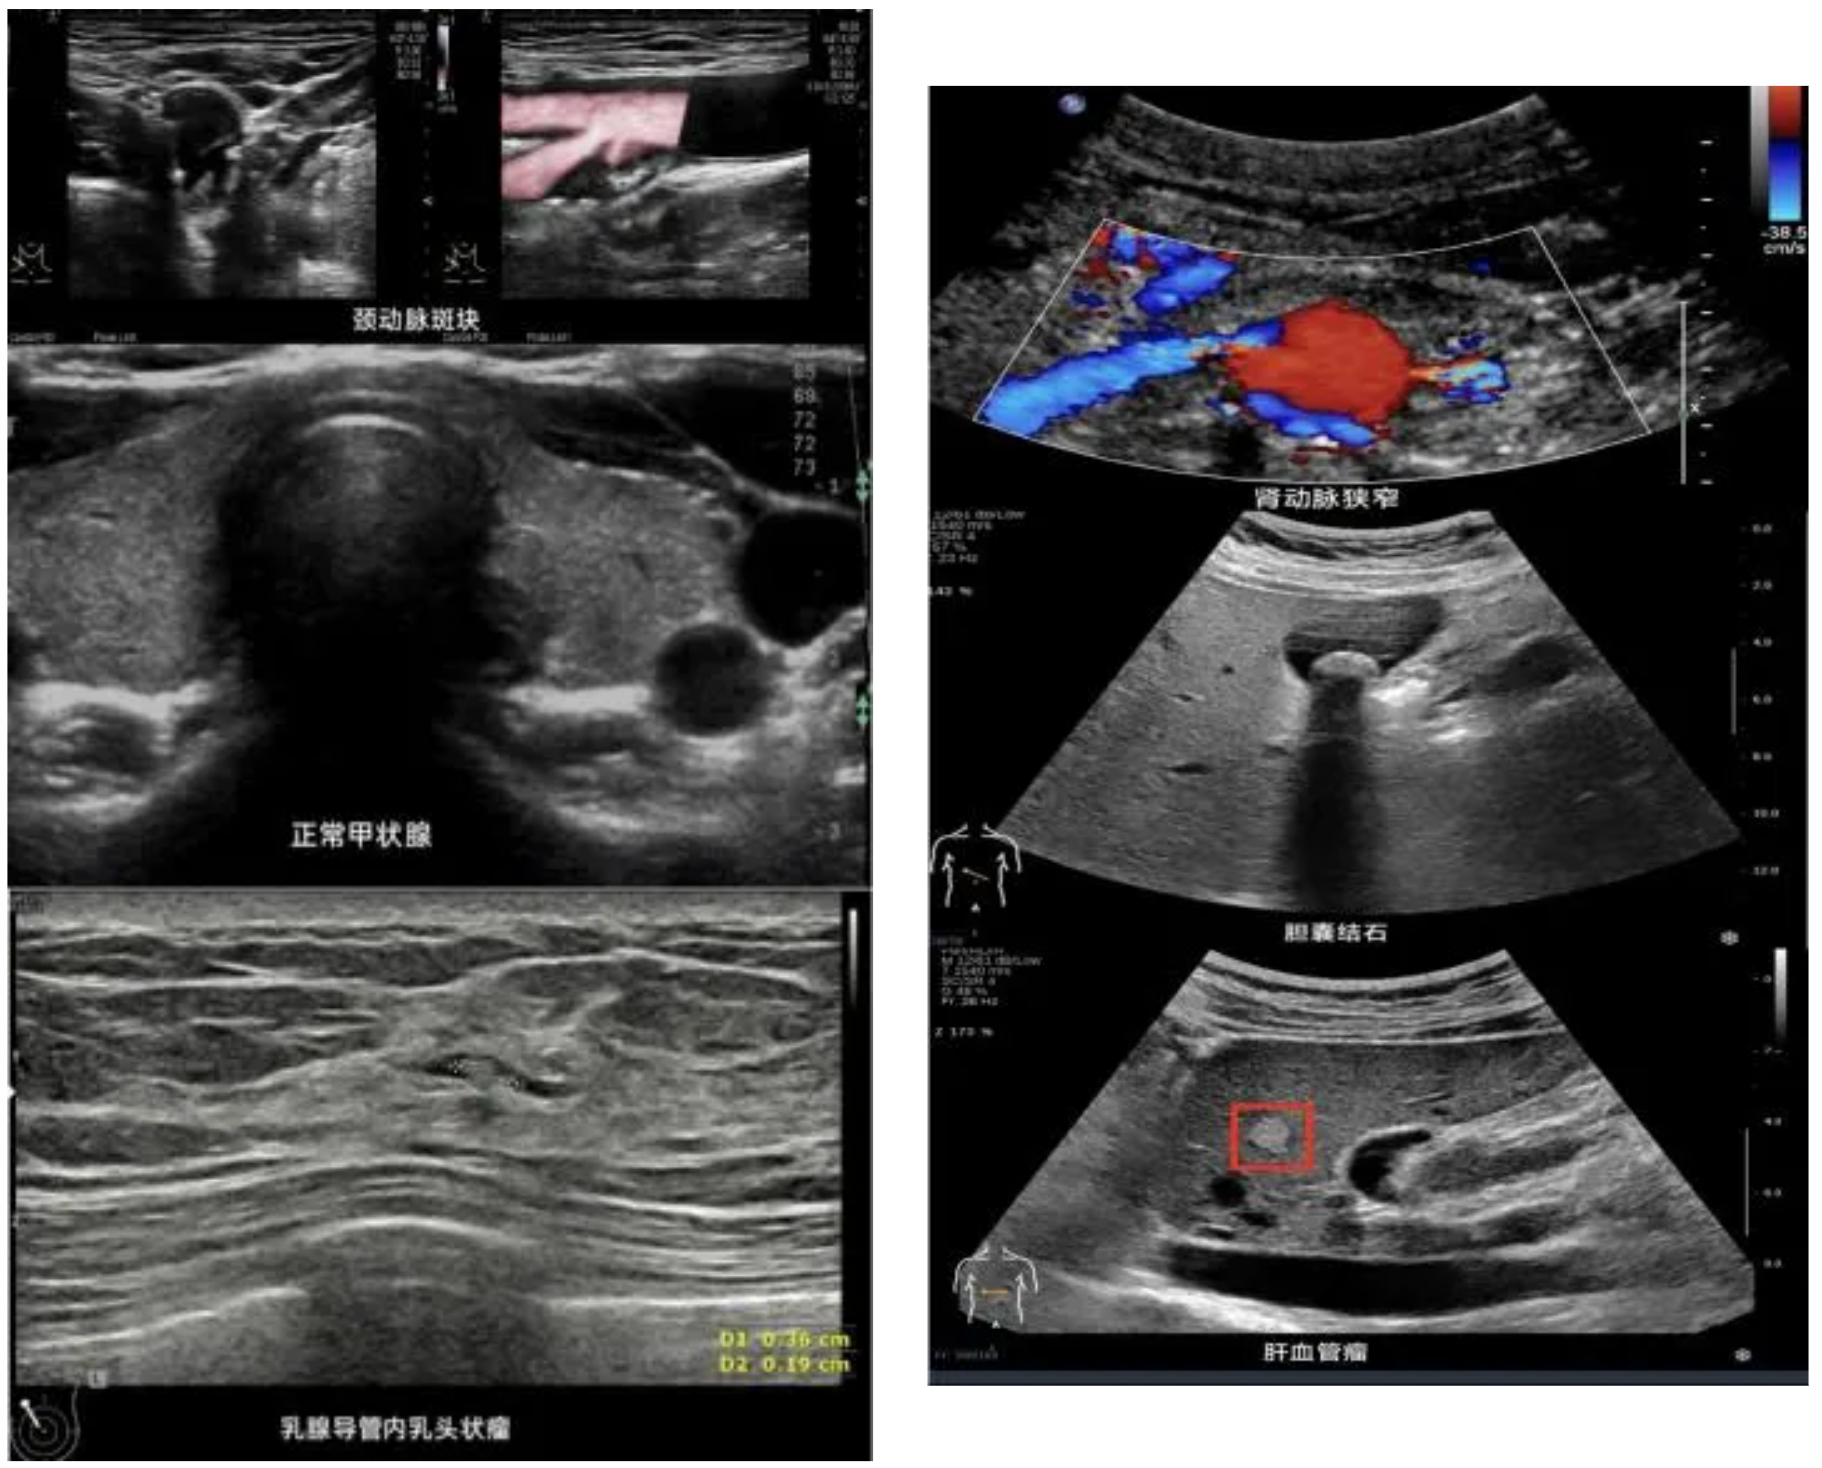

1.腹部超声检查:这是最广为人知的检查项目,堪称“基础款”,肝、胆、胰、脾、双肾等,排查脂肪肝、结石、肿瘤等,需要空腹进行,以保证图像清晰。另外,还有胃充盈超声检查,可以清晰地显示胃壁层次结构以及病变,是胃镜的较好补充检查方法。

2.浅表器官超声检查:甲状腺、乳腺筛查结节的首选方法,评估涎腺(腮腺、颌下腺)、淋巴结、男性睾丸与附睾等。

3.血管超声检查:血管的“交通督察”,动脉:看有无斑块(动脉硬化)、狭窄或堵塞。静脉:看有无血栓、静脉曲张及瓣膜功能。是无创诊断血管疾病的“利器”。